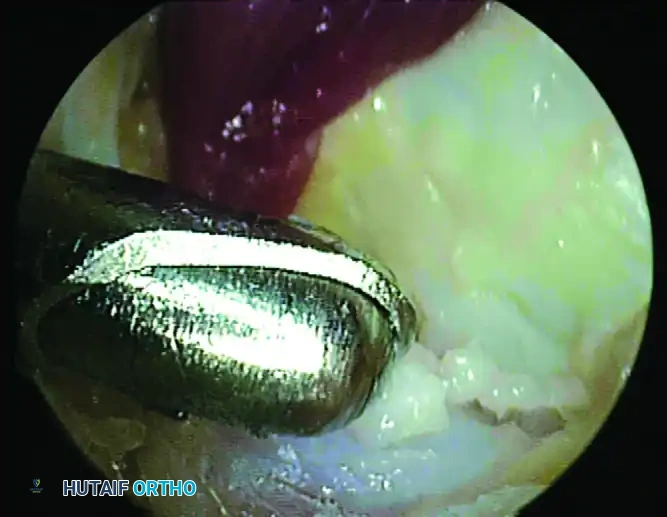

Step 3: Excision of the Os Trigonum / Stieda Process

Once the FHL is protected, direct attention to the bony impingement. To mobilize and remove the os trigonum, you must systematically detach its soft tissue tethers:

1. Partially detach the posterior talofibular ligament (PTFL).

2. Release the posterior talocalcaneal ligament.

3. Release the flexor retinaculum to fully expose the bony fragment.

Use an arthroscopic grasper to assess the mobility of the os trigonum. If it is fused (a Stieda process), use an arthroscopic burr or an osteotome to resect the prominent bone until it is flush with the posterior talar body. If it is a separate ossicle, use a combination of a shaver, radiofrequency wand, and grasper to shell it out of its soft tissue envelope. Extract the fragment through the portal; if the fragment is large, the portal skin incision may need to be slightly enlarged.